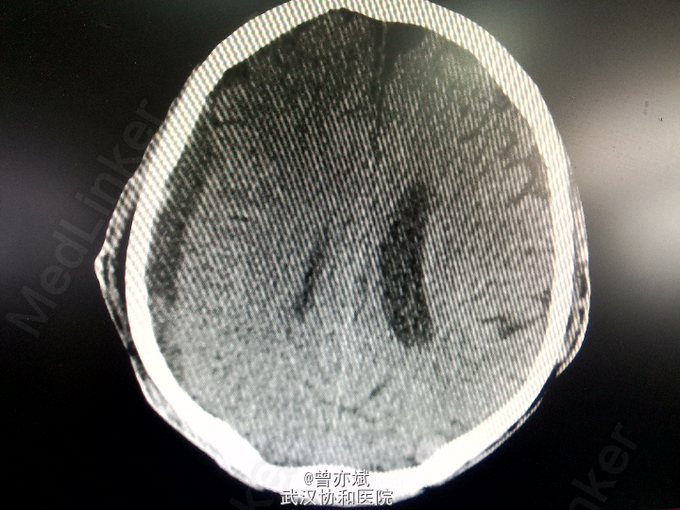

5天后的CT如下:血肿较前稍减少,密度稍减低 摔倒后当时无明显的症状,之后出现慢性硬膜下血肿,特别是在老年人中更易出现,摔倒后弱头部着地,应行CT检查。